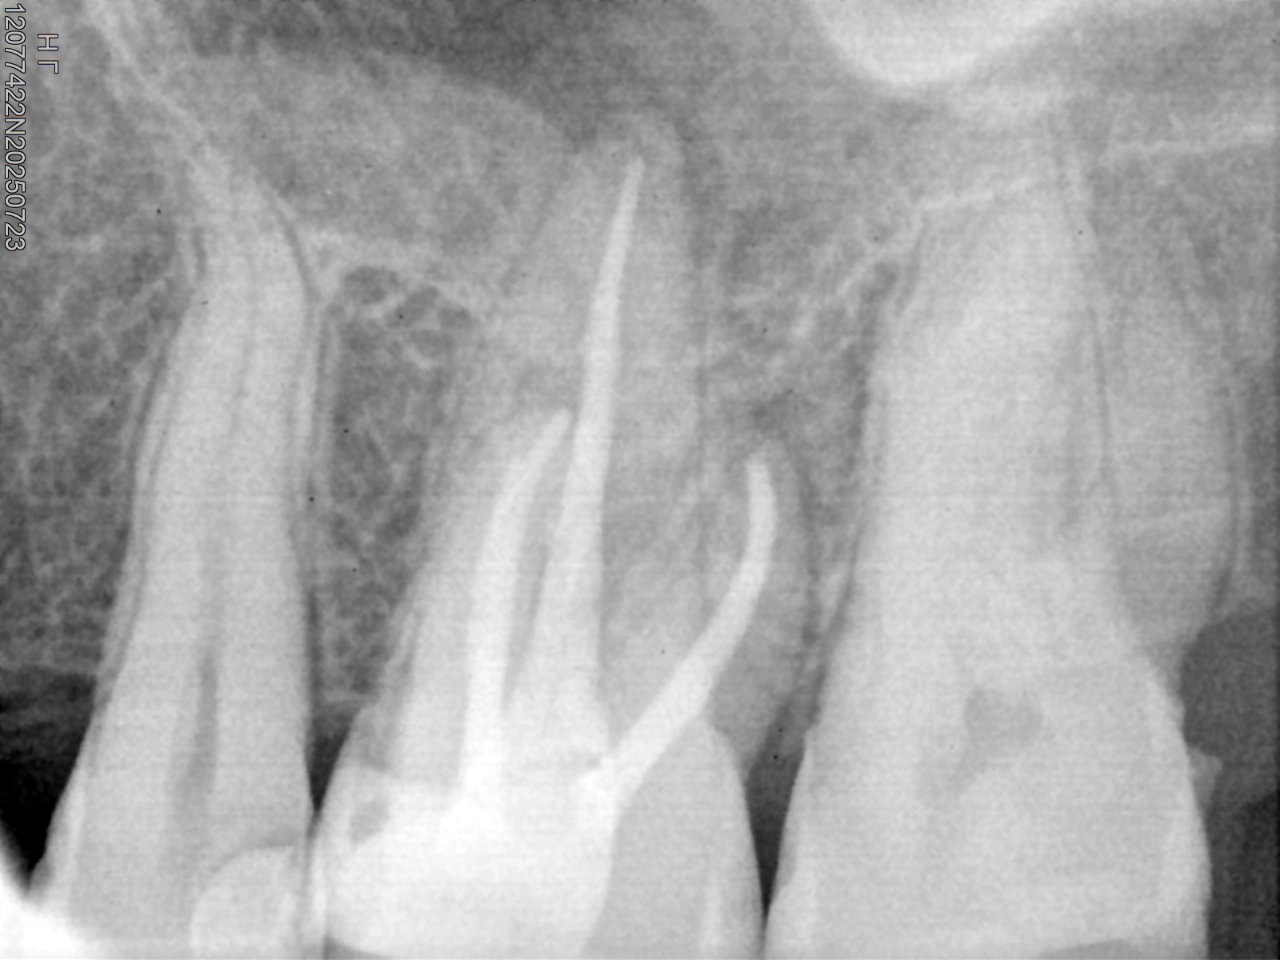

Working length determination

Treatment Approach: The retreatment procedure began with safe access refinement and complete removal of the existing gutta-percha. Thorough cleaning and shaping of the root canal system were performed, ensuring proper working length, apical patency, and effective disinfection.